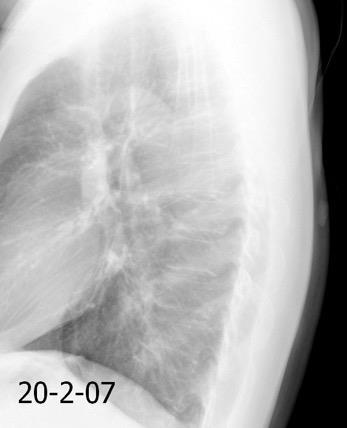

Normal